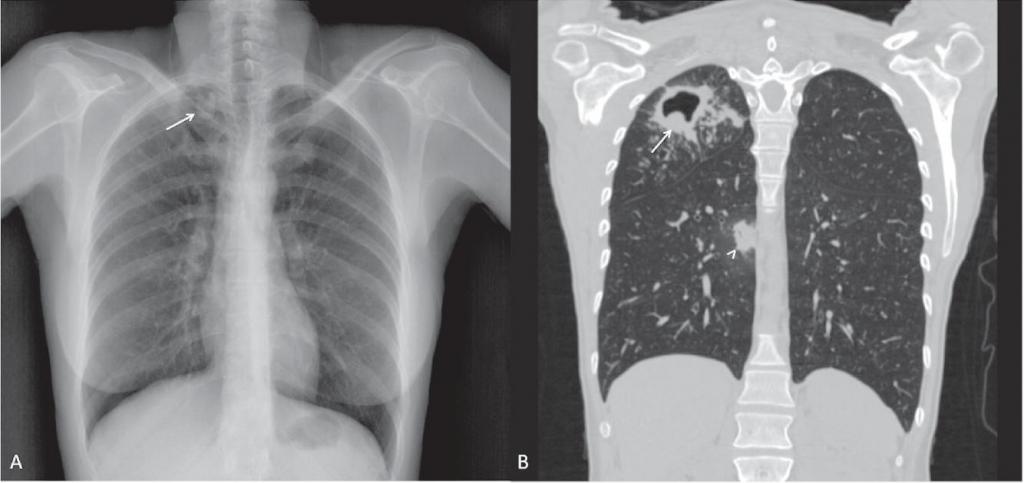

image

Ограниченный туберкулезный процесс в верхней доле правого легкого

В целом, в начале заболевания состояние заболевших детей и взрослых будет будет мало отличаться от здорового человека. Единственное обследование при данных формах туберкулеза, которое действительно способствует раннему обнаружению туберкулеза легких — это флюорографическое обследование (а еще лучше обзорная рентгенография органов грудной клетки). Именно поэтому флюорография легких входит во все медосмотры и профосмотры.